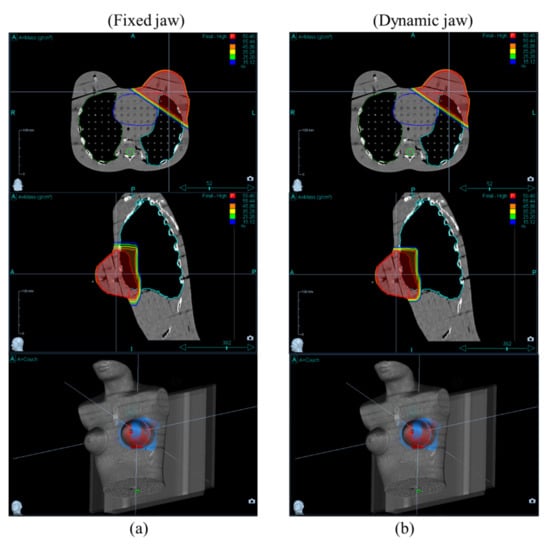

2.2. Treatment Planning

3. Results and Discussion

3.2. OARs Dose